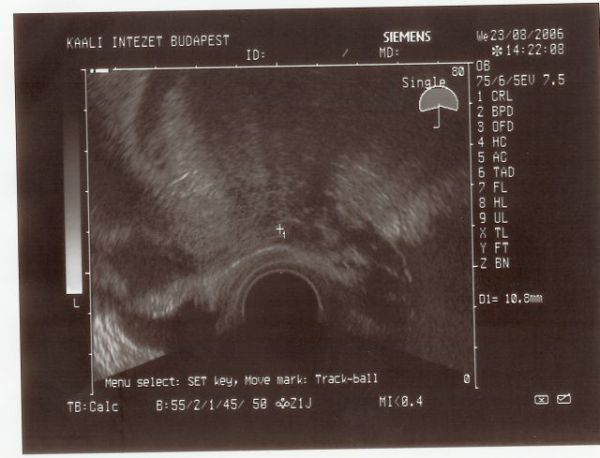

Wish, gratulálok a dobogó szívhez, innentől már egyenes az út, boldog áldott állapotot kívánok neked, minél kevesebb parával!